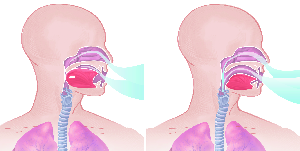

Über 860 Stichworte mit 120 Illustrationen auf 400 Seiten machen aus dem Lexikon der Lunge ein

wertvolles Werk.

Detailreiche Fotografien aus der medizinischen Praxis ergänzen die Texte; moderne, genaue,

wissenschaftliche Zeichnungen geben Einblick in die Anatomie und die Funktion der Lunge und

anderer Organe.